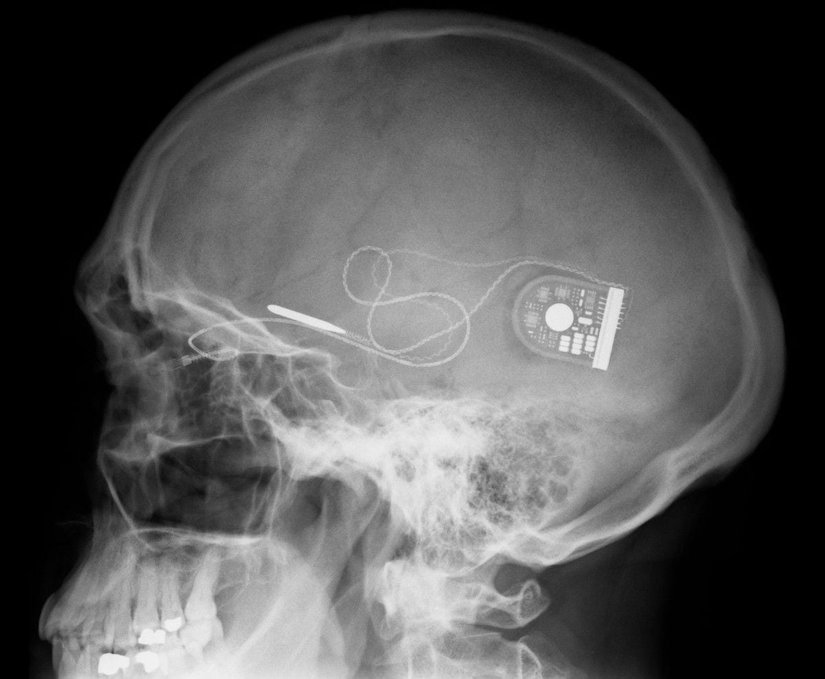

Bu cihaz, Serdans’ın beyninde globus pallidus adlı bölgeye düzenli olarak elektriksel sinyaller göndererek çalışıyordu. Cihaz düzenli olarak çalıştırıldığında Serdans yürümesinde hiçbir sorun yaşamıyor ve herhangi bir ağrı hissetmiyordu. Ancak cihaz yıllar sonra bir gün aniden çalışmamaya başladı ve Serdans, hemen o gün değişikliği hissetmişti. Serdans, ağrıları tekrar başlayınca eskisinden farklı yeni bir çözüm arayışına girdi ve bu sefer karşısına nöral implant çıktı.

Dünya üzerinde 100,000’in üzerinde insan derin beyin uyarımı implantlarıyla yaşamını sürdürüyor ve bunların çoğu Parkinson hastalığına sahip kişiler. Cihaz basit bir yapıya sahip, sadece derinin altına yerleştirilen bir pile bağlı bir çift kablodan ibaret. Cihaz hastalar için bir tedavi özelliği taşımak yerine beynin yaptığı işlevi taklit ediyor. Hastanın ilgili beyin bölgesine küçük elektriksel şoklar göndererek beynin yerine getirmekte zorluk çektiği işlevi telafi ediyor. Dahası sadece bir çift kabloyla 5 yıllık motor kontrol sapması tersine döndürülebiliyor.

Şimdi konunun bilimsel, tıbbi kısmından çıkalım ve implantlara farklı bir gözle yaklaşalım. İmplantlar daha önce bahsettiğimiz gibi sadece bir adet pil ve bir çift kablodan oluşuyor yani çok ucuz bir maliyete sahipler. İmplantların tıp dünyasına getireceği ekonomik tasarruflar kesinlikle göz ardı edilemez. Dünya’nın en büyük beyin uyarım cihaz üreticisi Medtronic, geçen yıl implantlardan 1.7 milyar dolar kazandı. Bu derece yüksek bir miktar elbette üretici firma için acaba cihazı çeşitli amaçlar için de kullandırabilir miyiz sorusunu akıllara getiriyor. Örneğin, şu an epilepsi hastalarında hasta nöbet geçirmeden önce ilgili elektrik sinyallerini algılayıp hastanın nöbet geçirmesini engelleyebilecek bir model üstünde çalışılıyor.